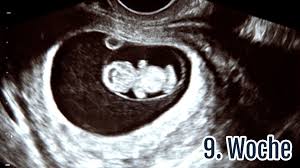

9 Ssw Die 9 Schwangerschaftswoche Ultraschall Symptome Tipps Netmoms De

SSW du musst dir vorstellen das ist ja in der 6. SSW es ist jetzt 47mm groß der errechnete Termin ist de 11413. Filme über das ende der welt. Das Baby ist in der 9. Ssw ist es gar erst 2 mm. Ssw beim fa war genau 6 wochen und 4 tage schwanger war das kleine erst 6 mm. 6 4 ssw ultraschall nichts zu sehen. Ssw Ende Mai rechnerisch 10 SSW sah. SSW ein Ultraschall durchgeführt wird und die Mutter das Herzschlagen ihres Kindes sehen kann.